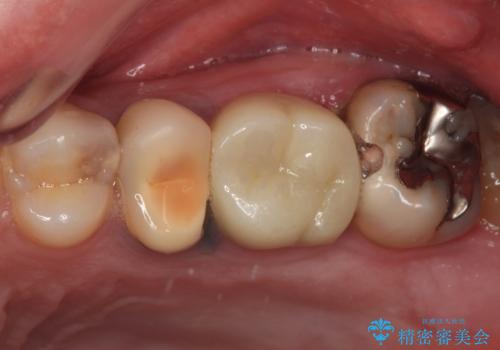

- 銀歯やむし歯でものが挟まるところが気になるとのことで来院された患者様です。

左上の奥歯は神経が失活しており、根管治療が必要な状態でした。

その他は銀歯のインレー(部分的な詰め物)が装着されており、それらはむし歯を除去した後にセラミックインレーにて修復治療を行い、左下と根管治療を行う左上の奥歯はオールセラミッククラウンにて補綴治療を行うこととしました。